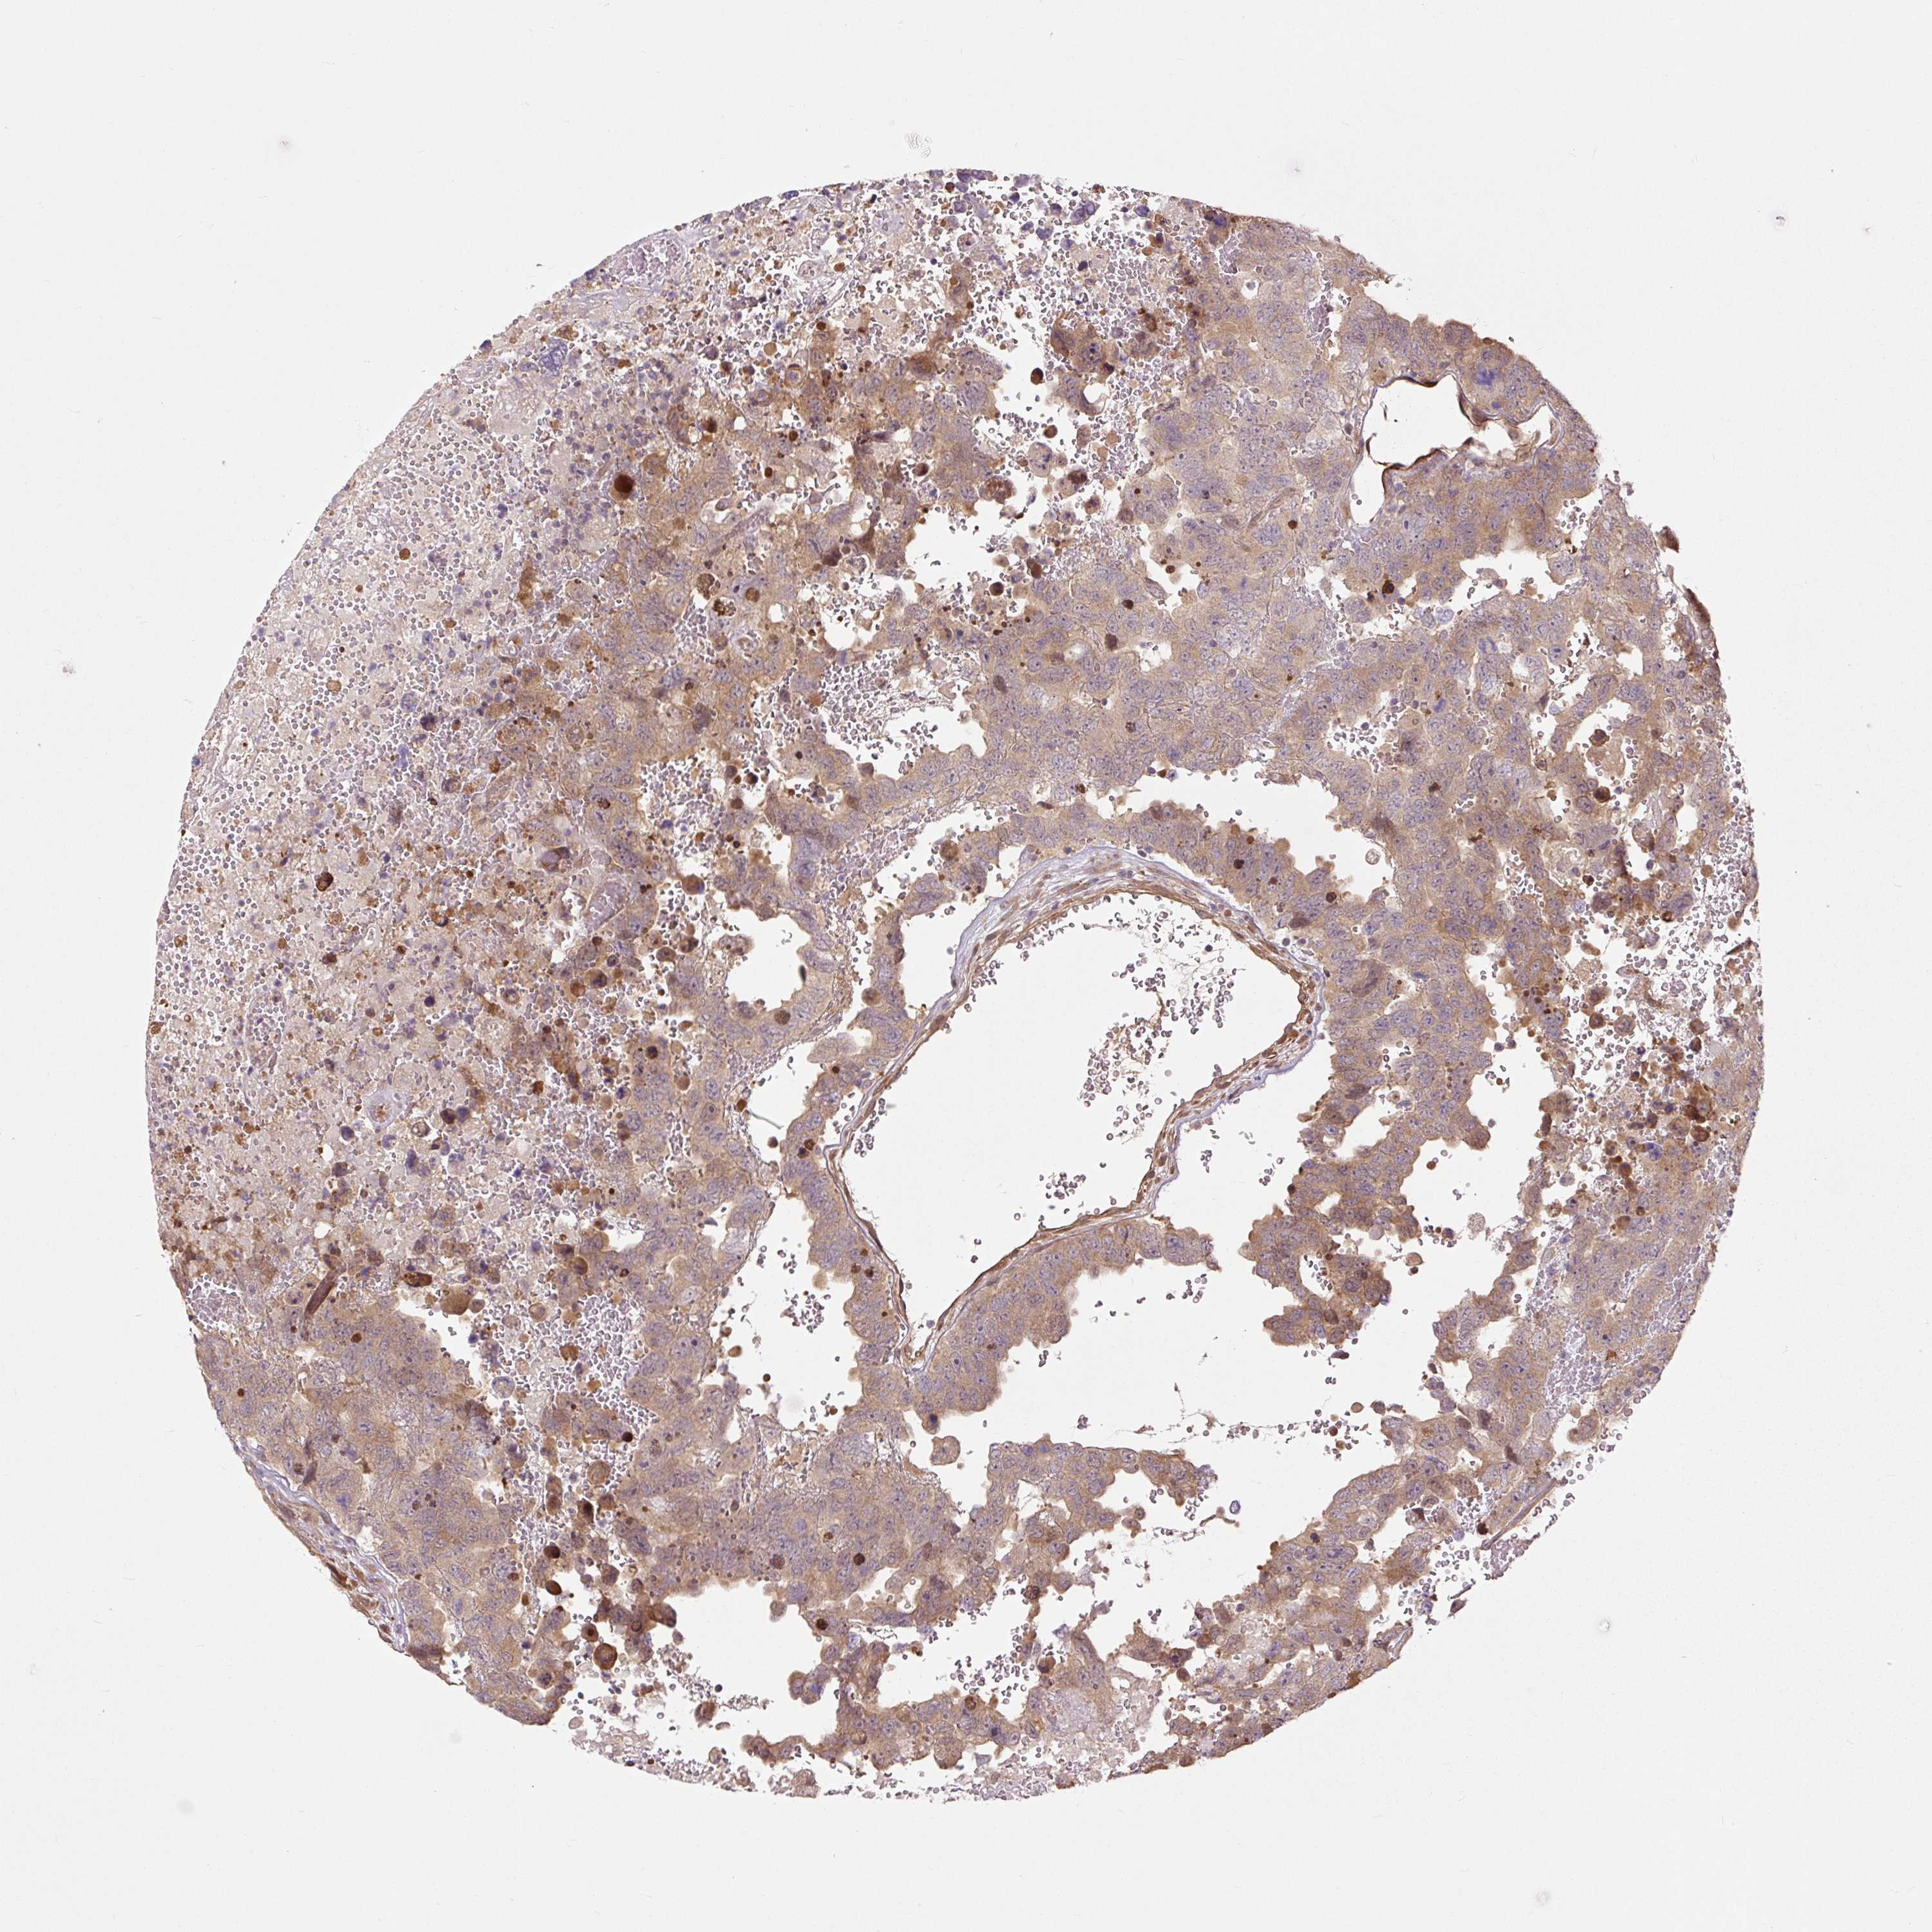

TESTIS CANCER - Protein expressioni

A mouse-over function shows sample information and annotation data. Click on an image to view it in a full screen mode. Samples can be filtered based on level of antibody staining by selecting one or several of the following categories: high, medium, low and not detected. The assay and annotation is described here.

Note that samples used for immunohistochemistry by the Human Protein Atlas do not correspond to samples in the TCGA dataset.

Antibody stainingi

Antibody staining in the annotated cell types in the current human tissue is reported as not detected, low, medium, or high, based on conventional immunohistochemistry profiling in selected tissues. This score is based on the combination of the staining intensity and fraction of stained cells.

Each image is clickable and will lead to virtual microscopy that enables deeper exploration of all samples and also displays staining intensity scores, fraction scores and subcellular localization as well as patient and tissue information for each sample.

Antibody HPA039437

Antibody HPA073929

Antibody CAB008364

Staining

High

Medium

Low

Not detected

Intensity

Strong

Moderate

Weak

Negative

Quantity

>75%

75%-25%

<25%

None

Location

Nuclear

Cytoplasmic/membranous

Cytoplasmic/membranous,nuclear

Carcinoma, Embryonal, NOS

Seminoma, NOS

Urothelial carcinoma, High grade